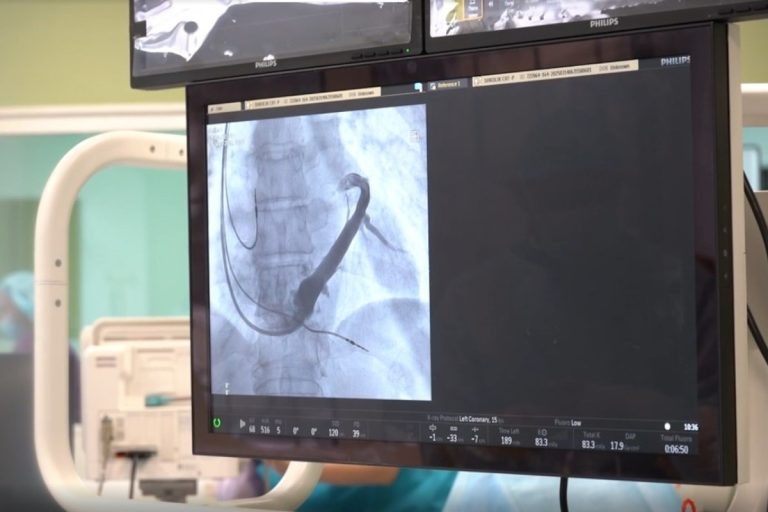

В клинике Тверского медуниверситета 14 марта команда аритмологов провела уникальную, первую в истории областной медицины операцию по имплантации трёхкамерного кардиостимулятора-ресинхронизатора.

Это устройство устанавливают под кожу в подключичной области, а электроды, подключённые к нему, имплантируют в три из четырёх камер сердца человека – правое предсердие и оба желудочка.

«Мы стараемся делать всё возможное, чтобы жители Верхневолжья могли получить этот достаточно сложный, высокотехнологичный вид помощи, не уезжая из региона. Клиника вуза развивается – мы создаём условия для пациентов, закупаем сложное навигационное оборудование, необходимое для проведения операций. Сегодня клиника оснащена электрофизиологической станцией и рентген-операционной с ангиографом (аппарат, который с помощью рентгеновского излучения визуализирует просвет сосудов и полостей сердца. – Ред.)», – отметил исполняющий обязанности ректора ТвГМУ Александр Сонис.